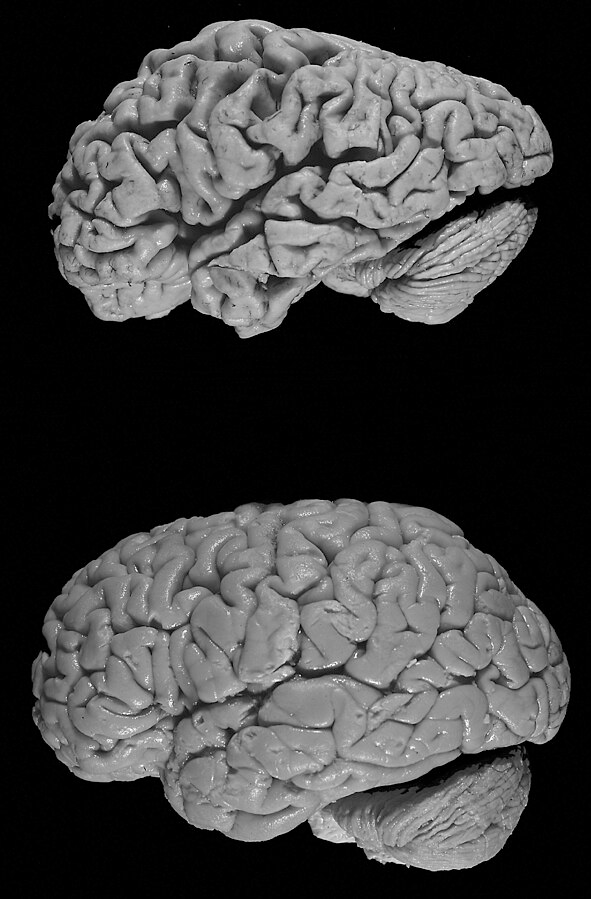

Aging is the main risk factor for some common brain diseases, but these disorders are more than just the natural slowing down of cognition that we expect to see with age. While Alzheimer’s and Parkinson’s diseases are generally thought of more as neurological disorders than mental illness, they affect many people in our society. In these “neurodegenerative” diseases, the neurons of a particular part of the brain begin dying off first, leading to a particular pattern of symptoms. In Parkinson’s disease, cells that produce the neurotransmitter dopamine deep in the brain die off for unknown reasons. At first, this causes problems with movement (like tremors, trouble walking, or stiff muscles) in regions that rely on dopamine to function, but cell death can eventually spread to other regions. In Alzheimer’s disease, cell death starts in the hippocampus, leading to particular symptoms related to memory. Eventually, the disorder spreads to many areas of the cerebral cortex responsible for tasks such as language, reasoning, and social behavior, creating a wider range of symptoms as the disease progresses. There are currently some treatments that can slow down the progression of these diseases, but no real cures. However, in both disorders, misfolded clumps of protein spread throughout the brain, which are targets for potential treatments. Scientists are also beginning to use brain scans like PET to look for these protein clumps in the brains of living patients. In the future, this may be a method of diagnosing patients based on more than just their symptoms.

Compare a healthy brain (bottom) to the brain of a donor with Alzheimer's disease (top). As cell death spreads to different regions, the brain appears to shrink in size. Image credit: Hersenbank/Wikimedia Commons. This file is licensed under the Creative CommonsAttribution-Share Alike 3.0 Unported license.